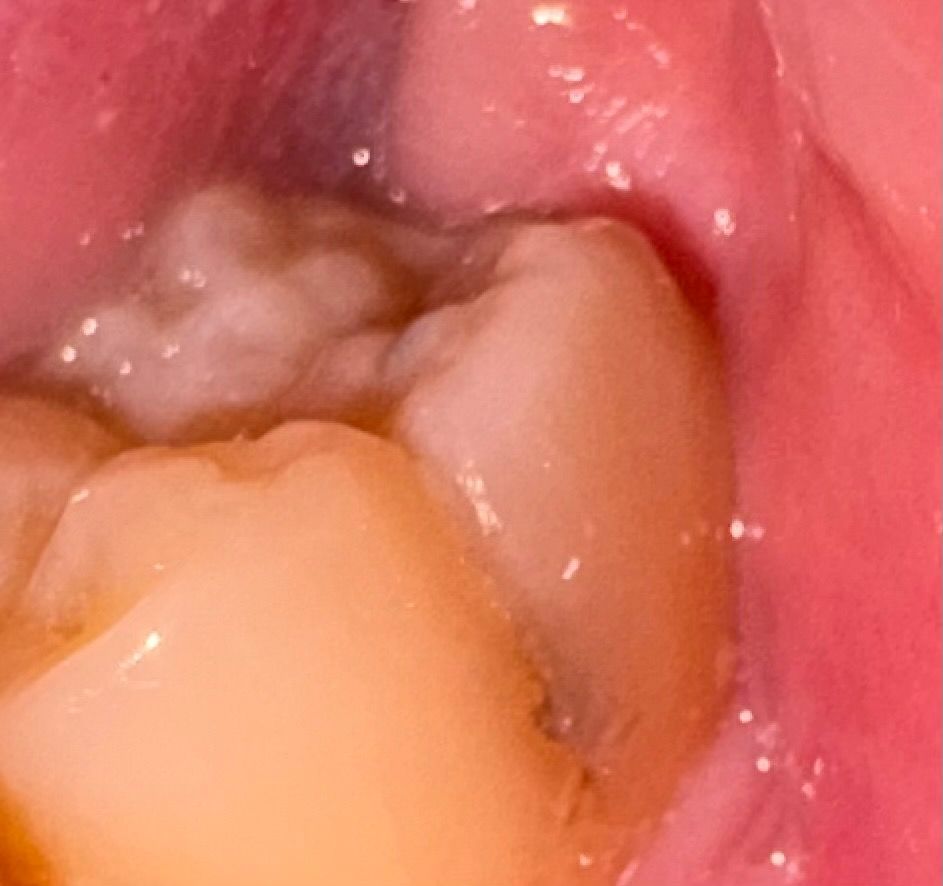

충치같은데 이정도면 신경치료 받아야하나요

통증 있었던 적은 없고 예전엔 어금니 위에 까만 점만 있었는데 이제는 옆면이 어둡게 되었더라고요 내부까지 충치 퍼진것같은데 신경치료 해야하나요

• 2번 째 사진

충치는 명확히 있는 것으로 판단되며 빠른 시일내에 치료를 받는 것이 필요해보이는 상황입니다.

정확한건 치과에 가셔서 엑스레이를 찍어봐야 알겟지만 신경치료 까지는 안하셔도 될것같습니다

통증 있었던 적은 없고 예전엔 어금니 위에 까만 점만 있었는데 이제는 옆면이 어둡게 되었더라고요 내부까지 충치 퍼진것같은데 신경치료 해야하나요 -> 생각보다 파보면 깊을 것 같습니다 신경치료 가능성도 있습니다